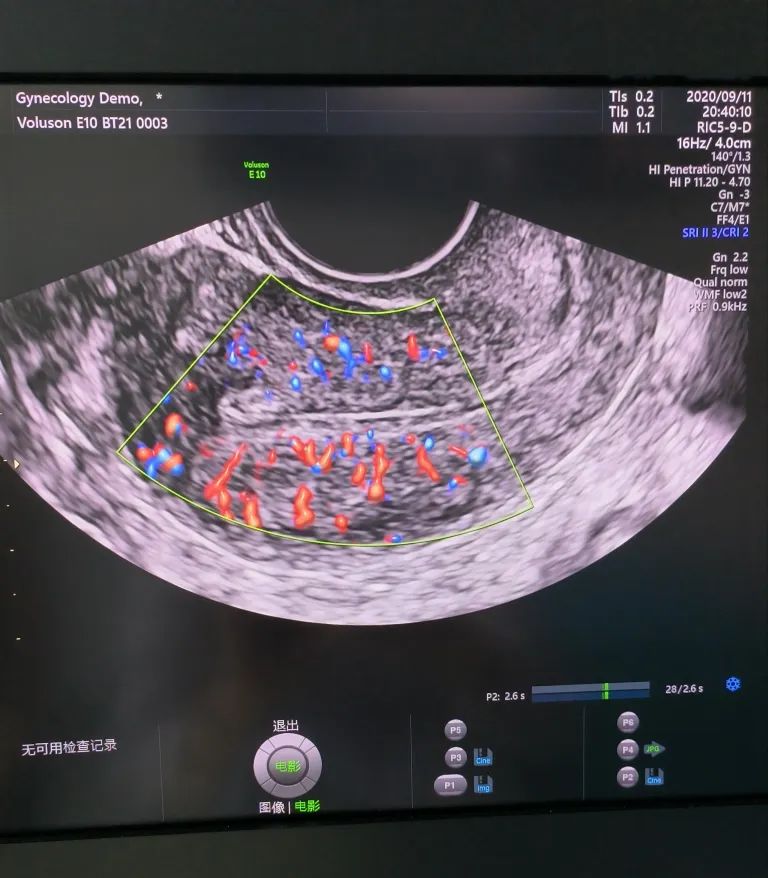

經(jīng)陰道超聲是在陰道超聲探頭上套上避孕套,將探頭伸入陰道進(jìn)行檢查。由于探頭位置接近子宮和卵巢,圖像更清晰,檢查結(jié)果更準(zhǔn)確。而且不需要憋尿,相對(duì)節(jié)省時(shí)間。所以現(xiàn)在大部分醫(yī)院對(duì)有性生活史的婦女更愿意開展經(jīng)陰道超聲檢查。